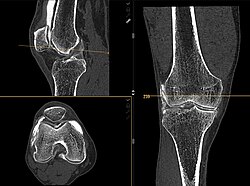

Koronal reformatierte Darstellung von Abdomen und Becken; gut zu erkennen sind u. a. die Leber und die beiden Nieren. -

Kombination aus multiplanarer Reformatierung und sliding thin slab. Der Bildkursor befindet sich in der Harnblase. Die Originalschichtdicke beträgt 1,25 mm, dargestellt wird in allen Ansichten gemittelt (= average) in 3,7 mm bzw. 3,8 mm Dicke. -